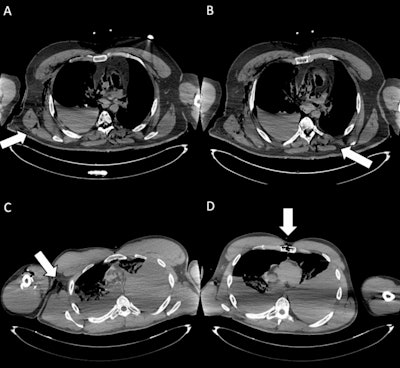

Exit wounds. (A) Axial CT scan shows an exit wound in the subcutaneous soft tissues at the root of the right thigh (white arrow). (B) Axial CT image depicts an exit wound in the left supraclavicular region (white arrow), visible as a focal soft-tissue defect with surrounding gas bubbles. (C) Cross-sectional CT slice illustrates an exit wound at the left posterior abdominal wall (white arrow), with subcutaneous emphysema and adjacent soft-tissue disruption. (D) CT image demonstrates an exit wound in the right chest region (white arrow), characterized by soft-tissue laceration and subcutaneous gas. Exit gunshot wounds were associated with the lowest inter-reader agreement (Fleiss’ kappa = 0.36). Despite the very high specificity of virtopsy, sensitivity was particularly low among readers without forensic experience (12.5% and 16.7%), underlining the difficulty in correctly identifying these injuries on postmortem CT.